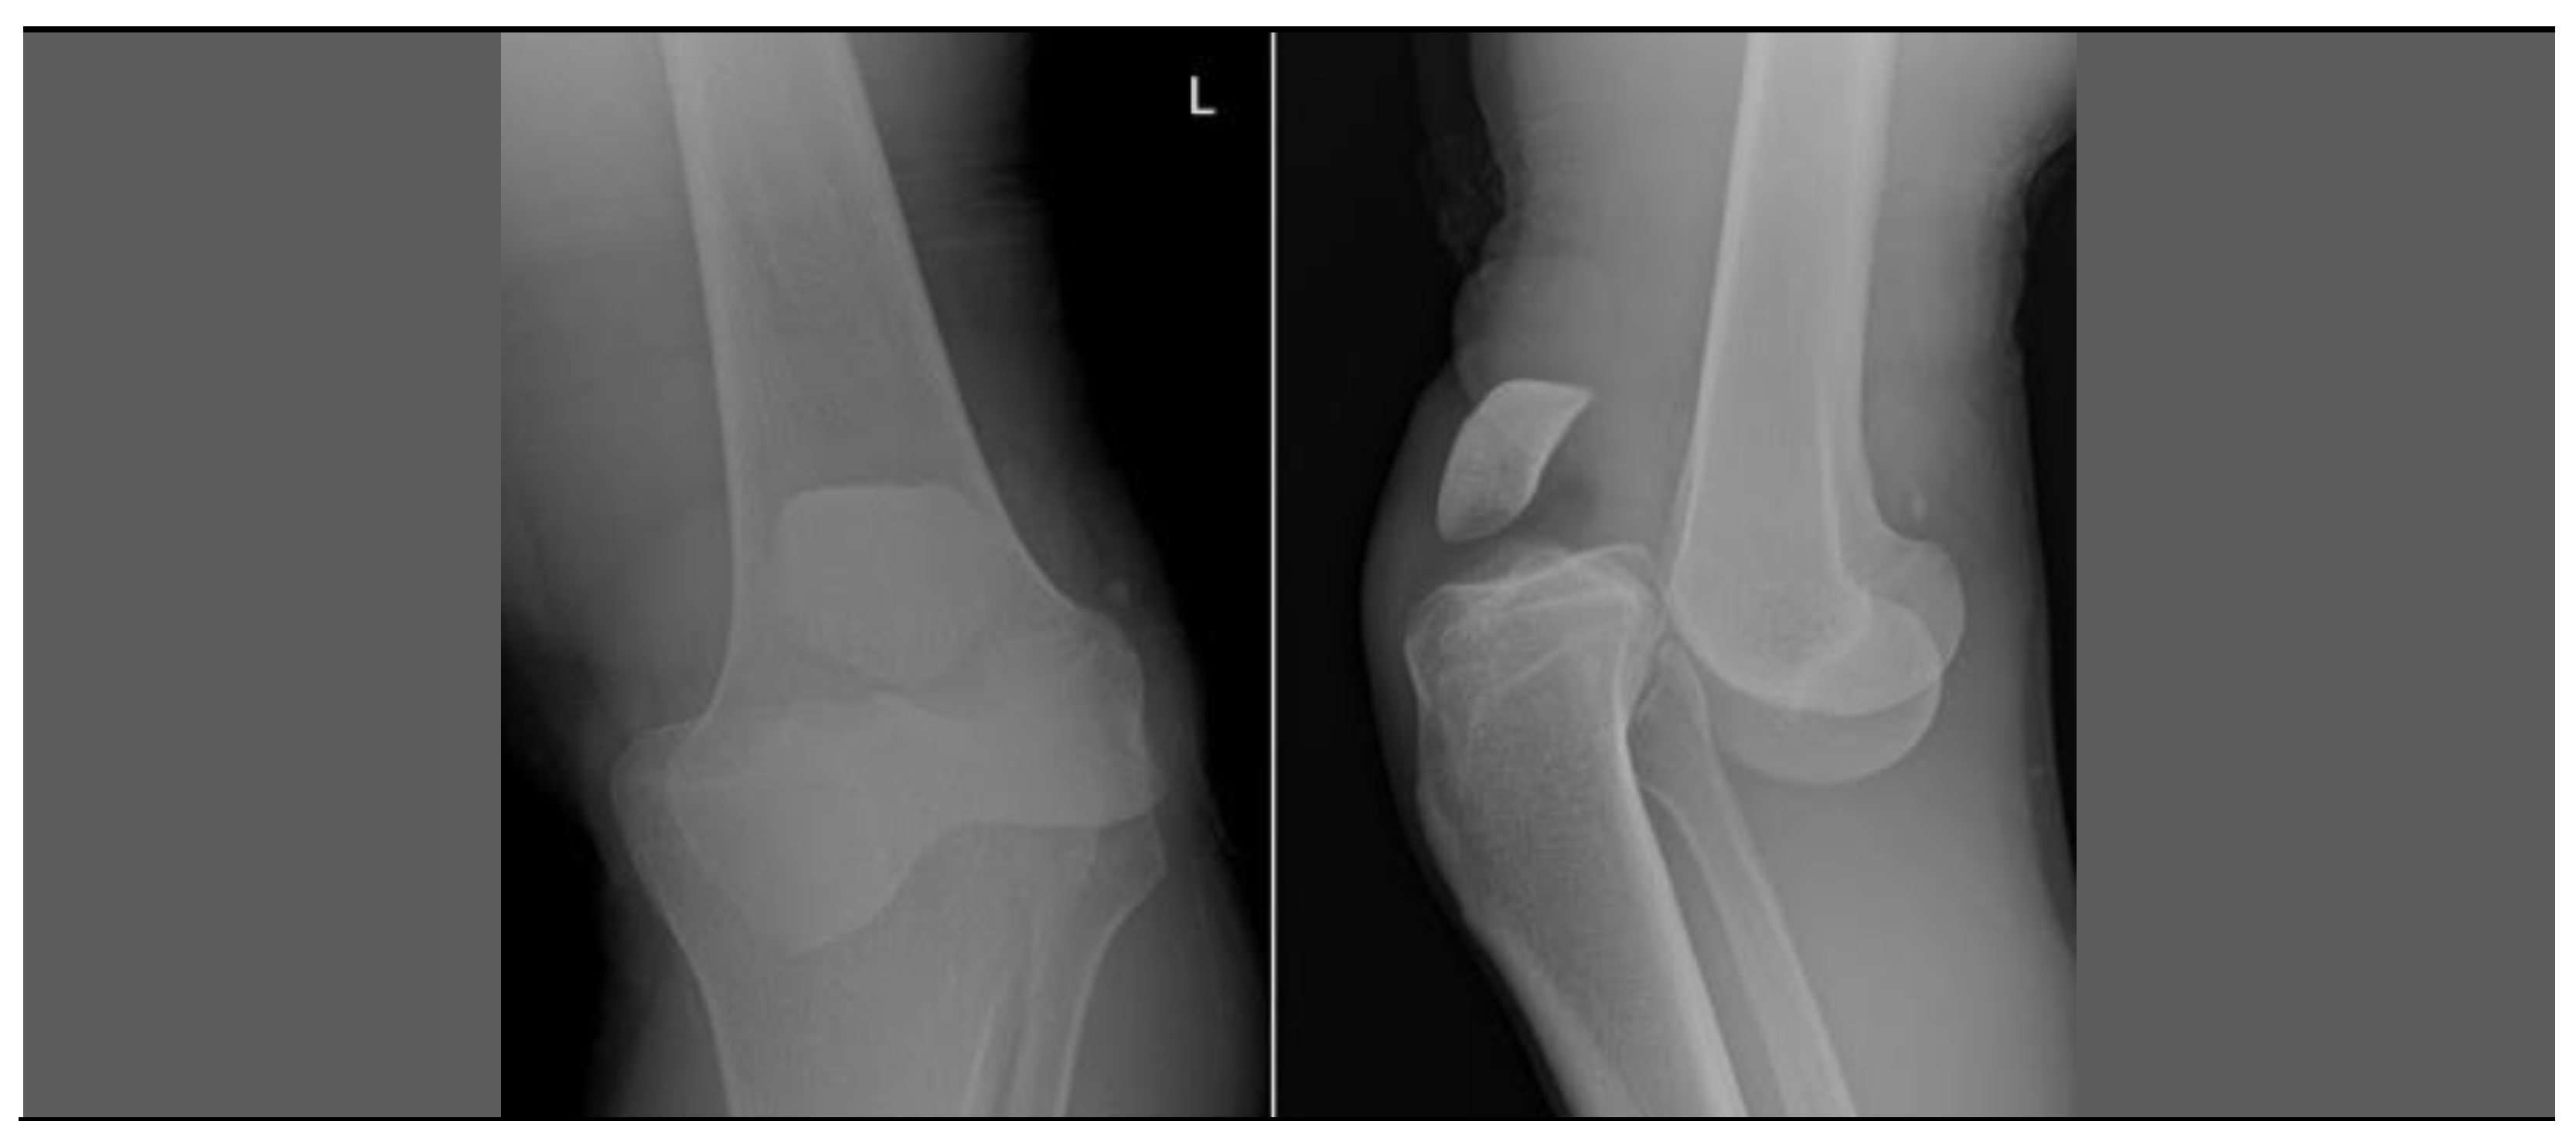

2.2. Second Case—Severity of Disease